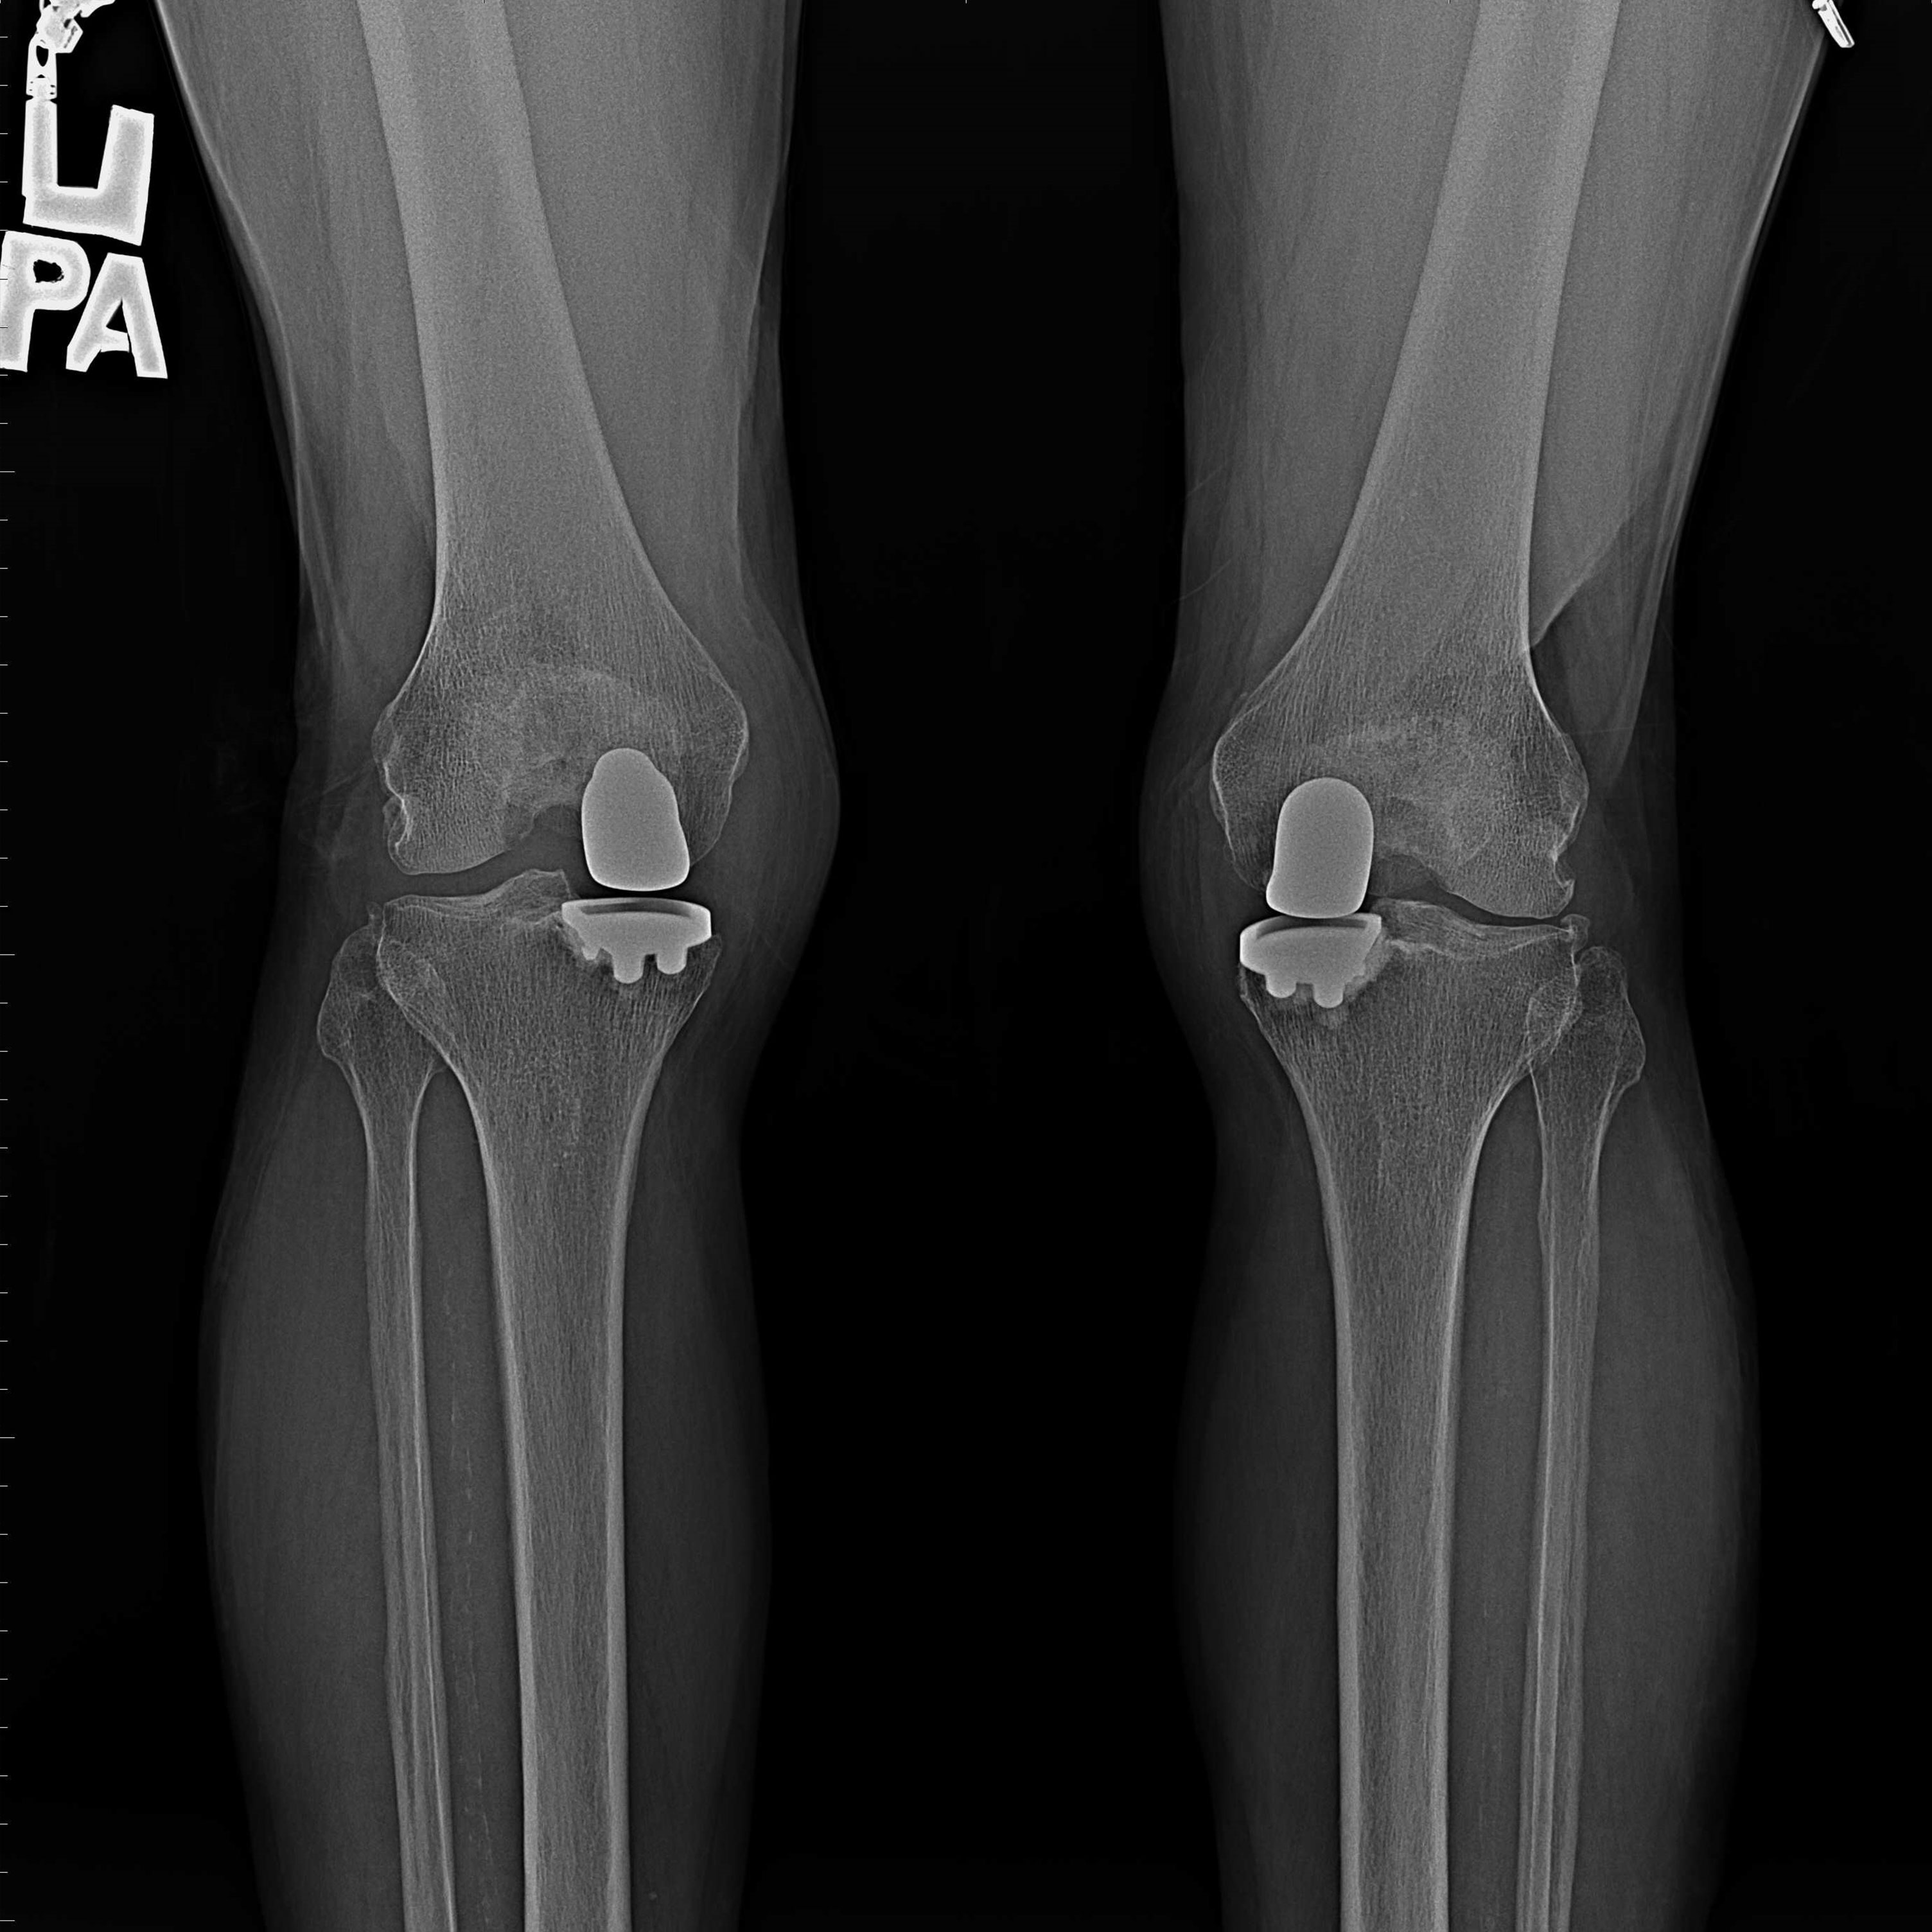

機器手臂手術 首頁 案例分享 膝關節手術 機器手臂手術 蔡女士 78歲 術前 術後 陳女士 70歲 術前 術後 術前 術後 ANGEVINE女士 73歲 術前 術後 U.S.A Mark 73歲 術前 術後 藍女士 78歲 術前 術後